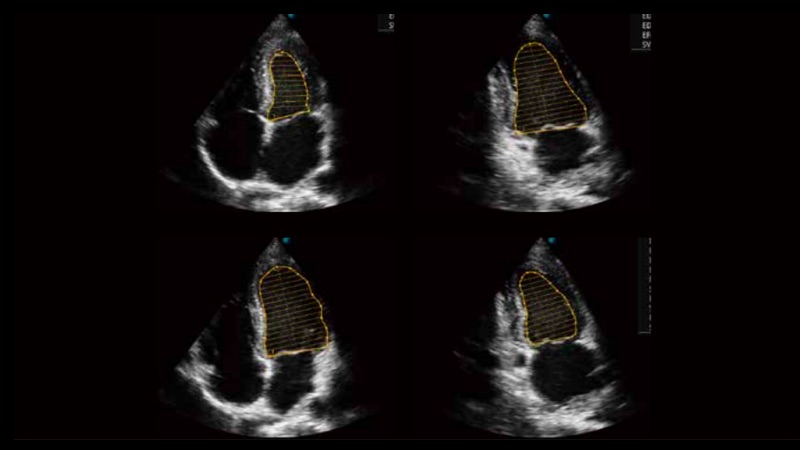

自動識別收縮和舒張末期心肌內膜,自動計算射血分數EF值。